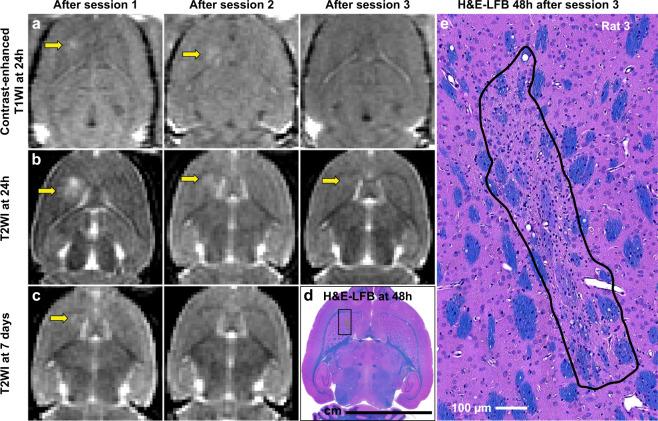

We investigated controlled blood-brain barrier (BBB) disruption using a low-frequency clinical transcranial MRI-guided focused ultrasound (TcMRgFUS) device and evaluated enhanced delivery of irinotecan chemotherapy to the brain and a rat glioma model. Animals received three weekly sessions of FUS, FUS and 10 mg/kg irinotecan, or irinotecan alone. In each session, four volumetric sonications targeted 36 locations in one hemisphere. With feedback control based on recordings of acoustic emissions, 98% of the sonication targets (1045/1071) reached a pre-defined level of acoustic emission, while the probability of wideband emission (a signature for inertial cavitation) was than 1%. BBB disruption, evaluated by mapping the R1 relaxation rate after administration of an MRI contrast agent, was significantly higher in the sonicated hemisphere (P < 0.01). Histological evaluation found minimal tissue effects. Irinotecan concentrations in the brain were significantly higher (P < 0.001) with BBB disruption, but SN-38 was only detected in <50% of the samples and only with an excessive irinotecan dose. Irinotecan with BBB disruption did not impede tumor growth or increase survival. Overall these results demonstrate safe and controlled BBB disruption with a low-frequency clinical TcMRgFUS device. While irinotecan delivery to the brain was not neurotoxic, it did not improve outcomes in the F98 glioma model.

我们使用低频临床经颅 MRI 引导聚焦超声(TcMRgFUS)设备研究了可控的血脑屏障(BBB)破坏,并评估了伊立替康化疗药物递送至大脑的效果和在大鼠脑胶质瘤模型中的效果。动物接受了每周三次的 FUS、FUS 和 10mg/kg 伊立替康或单独伊立替康治疗。在每次治疗中,四个容积式超声波靶向一个半球中的 36 个位置。通过基于声发射记录的反馈控制,98%的声发射目标(1045/1071)达到了预先定义的声发射水平,而宽带发射的概率(惯性空化的特征)大于 1%。通过给药 MRI 对比剂后测量 R1 弛豫率来评估 BBB 破坏,发现超声波治疗半球的 BBB 破坏明显更高(P<0.01)。组织学评估发现组织影响最小。BBB 破坏后,大脑中的伊立替康浓度显著升高(P<0.001),但仅在<50%的样本中检测到 SN-38,且仅在过量的伊立替康剂量下才检测到。伊立替康与 BBB 破坏并不会阻碍肿瘤生长或增加存活率。总的来说,这些结果表明低频临床 TcMRgFUS 设备可安全且可控地破坏 BBB。尽管伊立替康递送至大脑并未引起神经毒性,但它并未改善 F98 脑胶质瘤模型的结果。